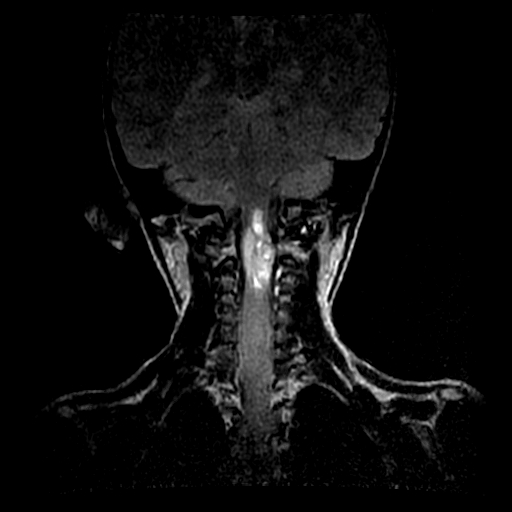

患者,男,5岁。左侧肢体无力10余天,无其他不适,头颅ct未见明显异常。

颈髓局限性增粗,呈混杂t1、混杂长t2信号,增强后不均匀强化。考虑胶质瘤。

髓内肿瘤,呈囊实性,增强实怀部分有强化,多考虑星形胶质瘤,不除外室管膜瘤